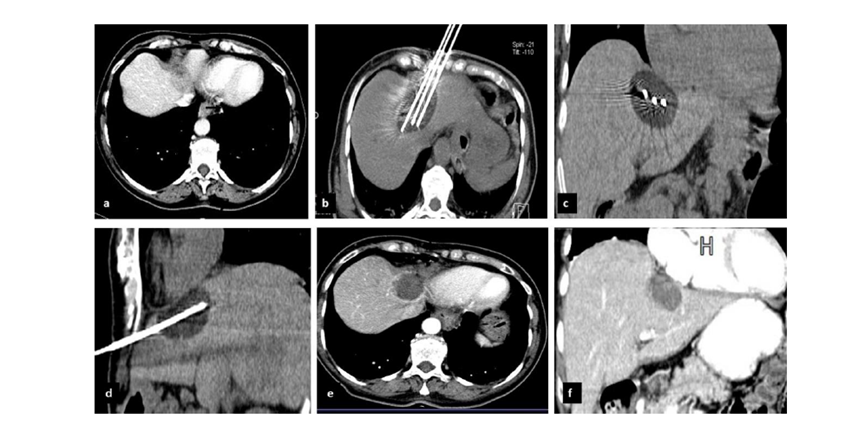

(A)動脈期CT圖像顯示有一個包膜下結(jié)節(jié)(箭頭)。(B)門靜脈期CT圖像顯示病灶區(qū)(箭頭)。(C) 在手術(shù)過程中的CT顯示一個冷凍探針位于病灶內(nèi)。(D)消融后,術(shù)后1個月影像CT顯示完全消融。患者在手術(shù)及住院期間無并發(fā)癥及重大并發(fā)癥發(fā)生。隨訪時間中位數(shù)為7個月(范圍:3-12個月),隨訪期間患者無局部腫瘤進展或死亡。

膽囊附近轉(zhuǎn)移灶(來自子宮頸癌)的冷凍消融術(shù)(A)門靜脈期 CT 圖像顯示膽囊附近有病變(箭頭)。(C) 手術(shù)過程中CT 顯示冷凍探針位于病灶內(nèi)。(D)消融手術(shù)后 1 個月CT 顯示完全消融。

CT引導(dǎo)的冷凍消融

(b) 冷凍消融術(shù)中影像顯示冰球完全覆蓋病變。(c) 19個月后隨訪,沒有發(fā)生局部腫瘤進展。完全消融率為97%(66/68);2名患者均接受了額外的冷凍消融,隨后實現(xiàn)完全消融。平均隨訪期為 12.8 個月(范圍:3-27 個月)。所有患者均接受影像復(fù)查(CT 或 MRI)。11個病灶(16.2%)檢測到局部腫瘤進展,6、12和18個月時的累積局部腫瘤進展率分別為4%、8.2%和20.5%。8例出現(xiàn)遠(yuǎn)處肝內(nèi)或肝外病變的患者接受經(jīng)動脈化療栓塞、經(jīng)動脈化療栓塞加射頻消融治療或全身化療。

62歲女性,肝轉(zhuǎn)移(卵巢癌)腫瘤的完全消融病例(a)軸向CT顯示病變位置毗鄰心臟和上腔靜脈(黑色箭頭)。(b)術(shù)中軸向CT掃描:使用三個冷凍探針。1個月后的軸向(e)和冠狀位(f)增強CT掃描顯示低密度區(qū)域,由于肉芽組織反應(yīng)引起的邊緣增強。